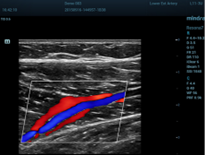

HR Flow (High Resolution Flow)

Τεχνική η οποία παρέχει αισθητά καλύτερη ποιότητα εικόνας στην PW Doppler και στην Colour Doppler απεικόνιση αυξάνοντας την ακριβή απεικόνιση των αγγείων και την ευαισθησία στην ανίχνευση της ροής αποτρέποντας την «υπερχείλιση» των αγγείων. Εφαρμόζεται σε όλες τις ηχοβόλες κεφαλές τύπου Convex, Linear, Microconvex καλύπτοντας όλο το φάσμα των διαγνωστικών εξετάσεων σε παιδιά και ενήλικες

Ηχοβόλος κεφαλή τύπου Linear Array L13-3N από 3,0 MHz έως 13,0MHz MHz με δυνατότητα επιλογής διαφορετικών συχνοτήτων στο B-Mode, Doppler, Έγχρωμο Doppler για απεικόνιση σε εξετάσεις και εφαρμογές για μικρά όργανα, αγγεία, κοιλία, νεύρα, μαστό, θυροειδή κλπ.